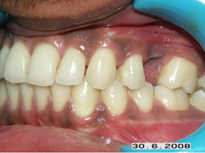

Your child has a beautiful set of teeth as a toddler but as he grows into adolescence you begin to notice an irregular arrangement of teeth. The canine teeth at the corner of the mouth looks especially irregular which looks distasteful.

Your assistant in office has protruding teeth, she is very conscious of it and she often covers her teeth with her hand when she speaks.

Two different problems - In the case of the child irregular arrangement of teeth not only looks unsightly but also makes the cleaning of teeth difficult. In the case of the office assistant the protruding teeth results in a lower self esteem. Both the result of the improper position of teeth or jaws.

Irregular Teeth

Protruded Teeth